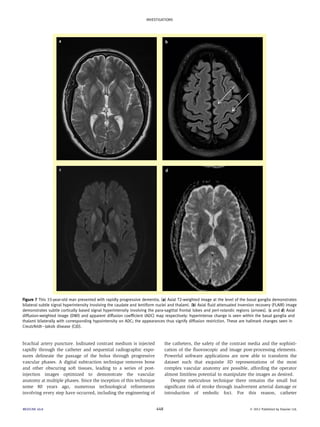

Figure 5 This 28-year-old woman presented with a history of headaches followed by progressive cerebral obtundation. There was a preceding history of

non-Hodgkin’s lymphoma. (a) Axial CT venogram (CTV) image at the vertex demonstrates irregular filling defects within the superior sagittal sinus

(arrows) with segments of non-opacification of the visualized cortical veins. The features are highly suggestive of sagittal sinus and cortical vein

thrombosis. (b) More inferiorly, a discrete filling defect is visible within the superior sagittal sinus e the ‘empty delta sign’ (black arrow). The superior

sagittal sinus is also expanded and hyperdense, suggestive of acute thrombosis. Scattered foci of para-sagittal parenchymal haemorrhage are also visible

(white arrows). (c) CTV midline sagittal maximum intensity projection image further demonstrates multiple filling defects within the superior sagittal sinus

(arrow). (d) Antero-posterior digital subtraction angiography (DSA) image depicting filling defects within the right transverse sinus and superior sagittal

sinus (arrows). A catheter has been placed within the right transverse sinus during attempted mechanical thrombectomy.